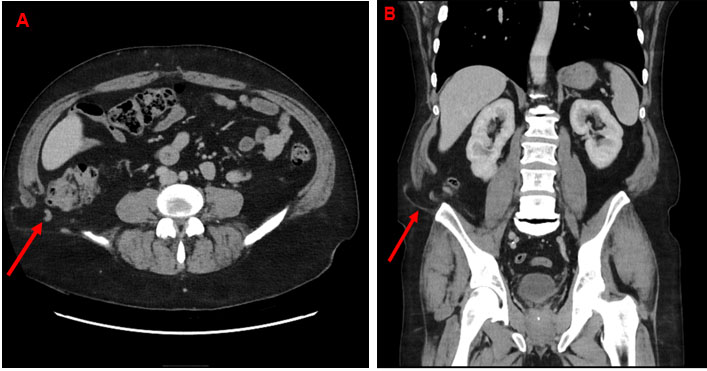

Anteroposterior radiographs of the pelvis showed an asymmetric enlarged right IPS with a focal area of osteolysis (Figure 1), raising suspicion of tumoral disease.

As observed in the Herneth study [3], pelvic magnetic resonance imaging (MRI) performed on a whole-body 1.5 T scanner (Avanto, Siemens Medical Systems, Erlangen, Germany) revealed hyperintense signal alteration of the bone marrow surrounding the right IPS on T2-weighted images, widening of the synchondrosis, and a hypointense band-line structure perpendicular to the pubic axis in the center of the IPS. Moderate hyperintense signals were also noted in the surrounding soft tissues (Figure 2). A computed tomography (CT) scan demonstrated focal enlargement of the right ischiopubic branch with central radiolucency and cortical thinning (Figure 3).

Figure 1: Anteroposterior radiograph of the pelvis demonstrating an asymmetric enlargement of the right ischiopubic synchondrosis (IPS) with a focal area of osteolysis.

Figure 3: CT scan demonstrates a focal enlargement of the right ischiopubic branch with central radiolucency and cortical thinning.